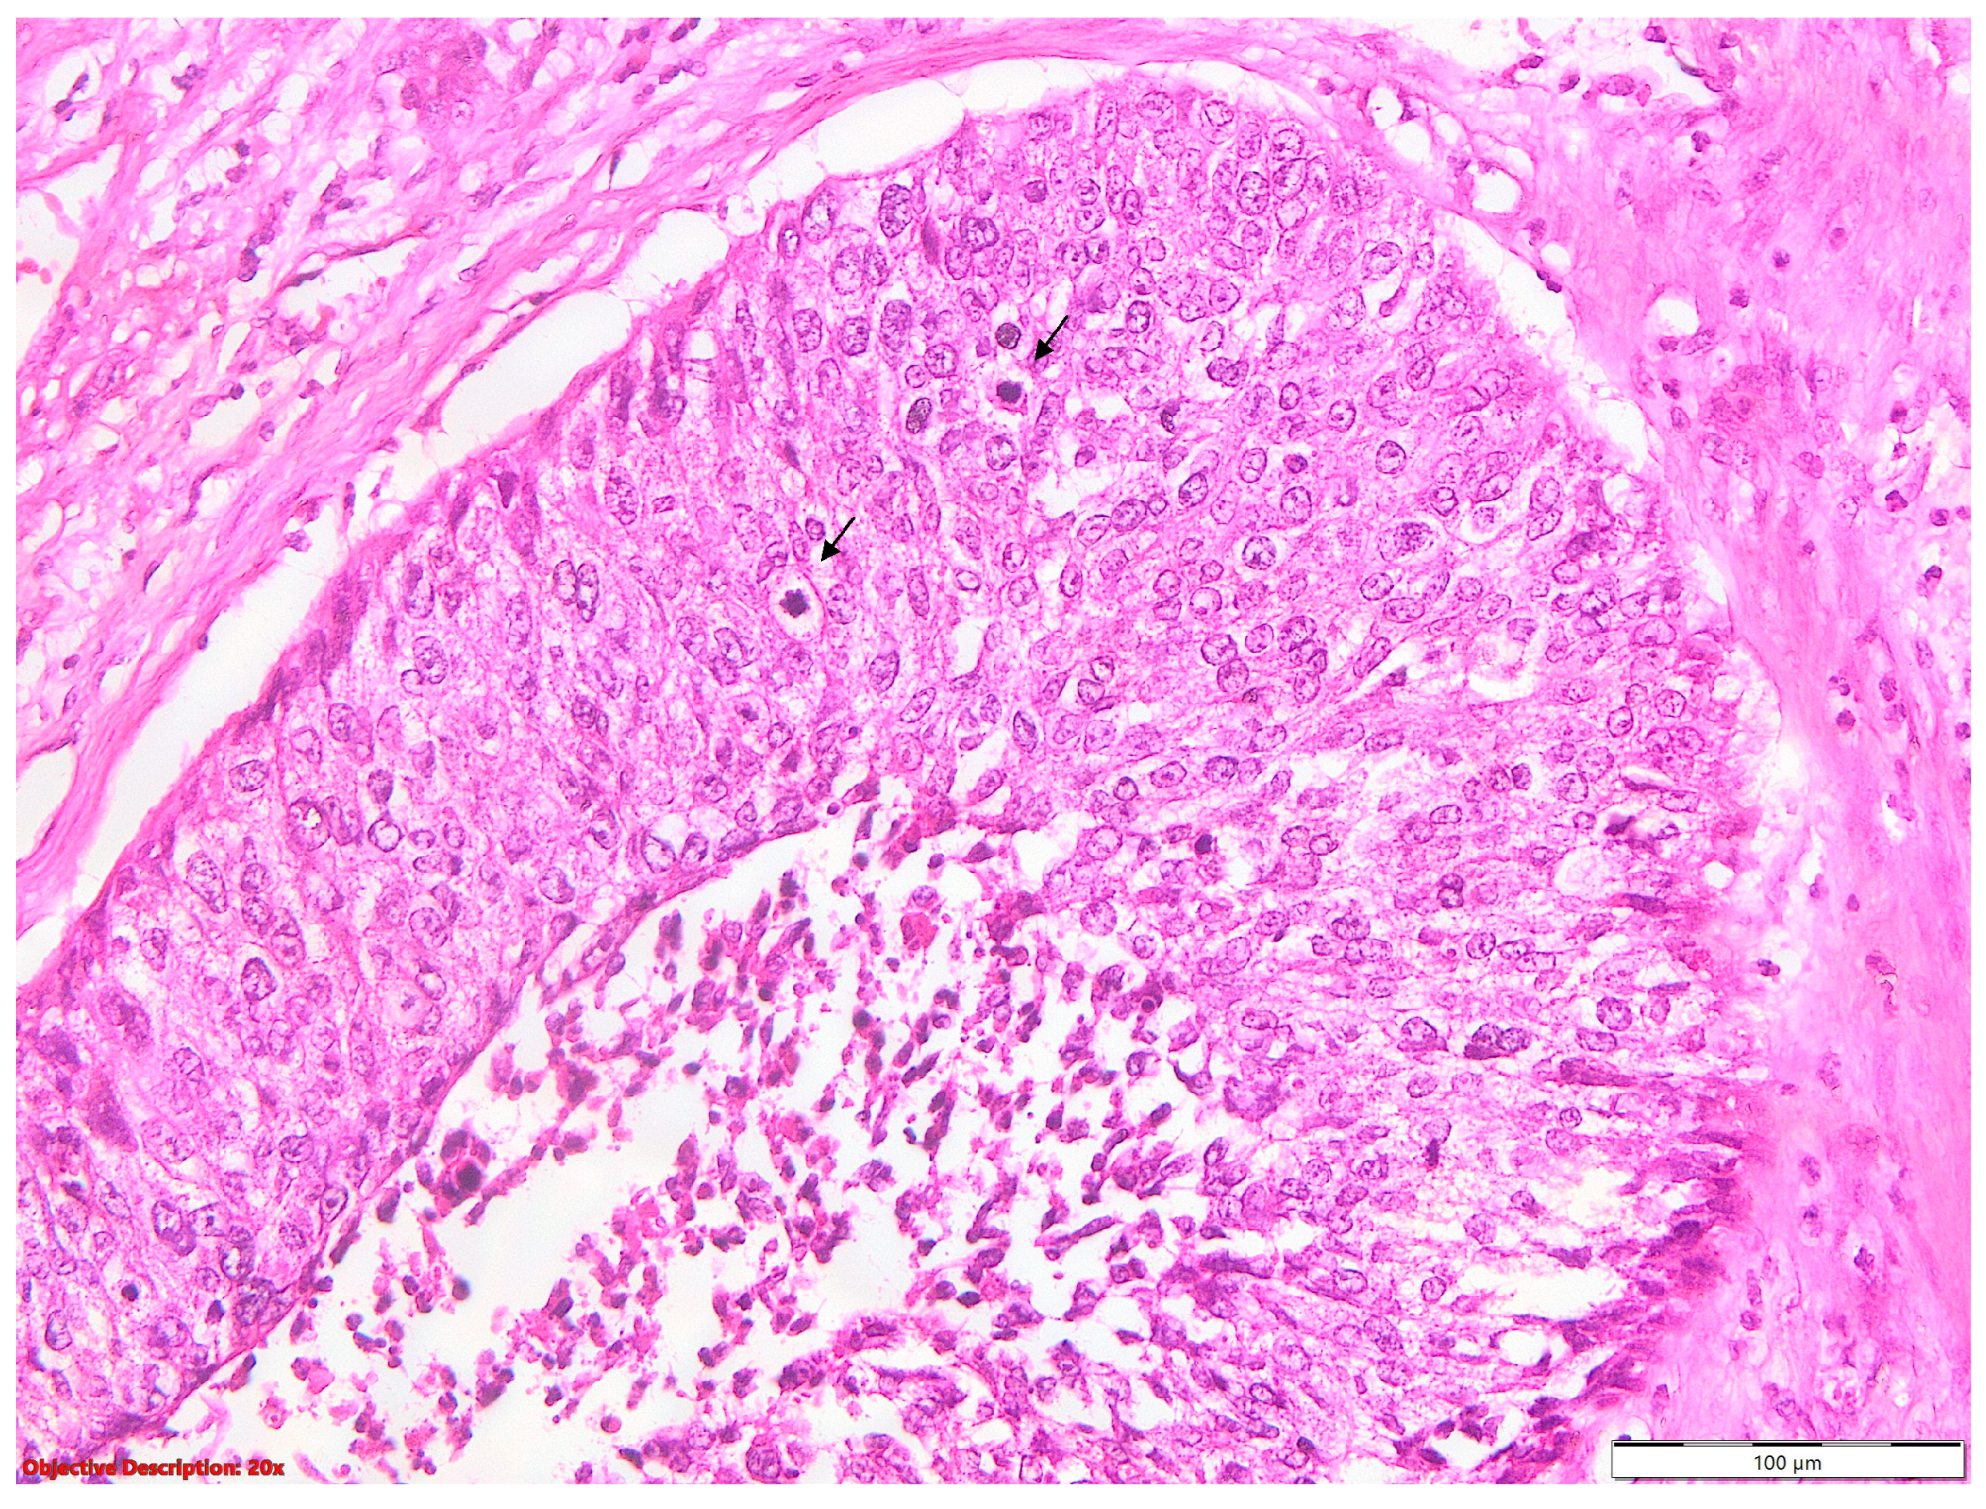

The presence of tumor budding (Figure 7) nearly tripled the hazard rate, while the STAS (Figure 8) increased it by approximately two times.

Figure 7. Tumoral budding in SQCC—small clusters or individual neoplastic cells (→) that are evident at the invasive front of a tumor; HE, 40×.

Figure 14 and Table 8 present the overall survival outcomes stratified by the presence or absence of tumor budding in patients with squamous cell carcinoma.

Patients with tumor budding have a higher mortality rate of 78.57% and a shorter RMST of 38.90. The median survival is 19 months (95% CI: 14.00 to 21.00).

Patients without tumor budding exhibit a lower mortality rate of 48.83% and a longer RMST of 75.50. The median survival is 108 months (95% CI: 50.00 to N/A).

These results indicate that the presence of tumor budding is associated with poorer overall survival outcomes in squamous cell carcinoma. The significant differences observed in the survival curves between the two groups underscore the prognostic relevance of tumor budding as a potential biomarker for predicting patient outcomes.